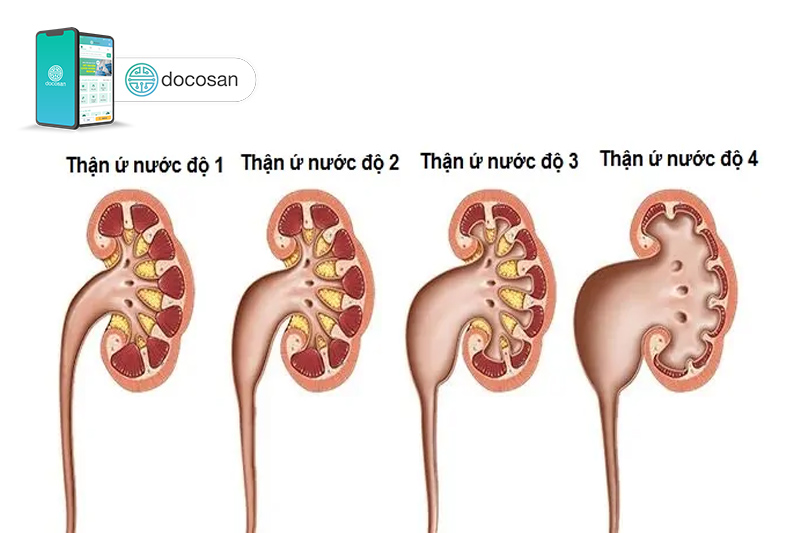

Thận ứ nước có nhiều mức độ với biểu hiện và các chữa trị khác nhau. Do đó cần có các phương tiện để xác định đúng mức độ.

Thận ứ nước có thể được chia làm 3 độ hoặc 4 độ, tùy vào hệ thống phân độ. Chính vì sự hiện diện của nhiều bảng phân độ khác nhau, có thể xảy ra hiểu nhầm khi diễn giải một độ thận ứ nước nào đó.

Tuy nhiên, bạn đừng lo lắng vì công việc diễn giải kết quả là của nhân viên y tế. Bạn chỉ cần biết rằng độ càng cao thì càng nguy hiểm (như thận ứ nước độ 3, thận ứ nước độ 4). Nhìn chung, độ 1 trong tất cả các hệ thống phân độ đều là tình trạng nhẹ, với những biểu hiện có thể không rõ ràng.

Trong khi đó, thận ứ nước độ 1 có thể không có triệu chứng, mà chỉ được phát hiện thông qua siêu âm (hay CT scan) khi xuất hiện giãn nở bể thận ở mức độ vừa nhẹ (5-7mm), bao gồm cả một vài đài thận. Tùy vào bên bị giãn nở bể thận mà gây bệnh thận trái ứ nước độ 1 hay thận phải ứ nước độ 1.